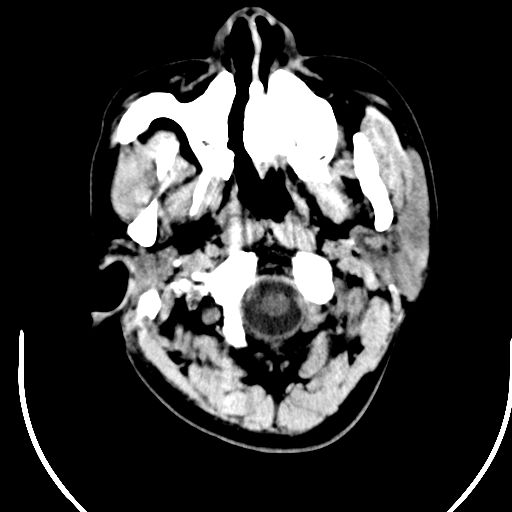

标题: CT25423:头部外伤意外发现右顶叶??? [打印本页]

标题: CT25423:头部外伤意外发现右顶叶???

ct值约13hu。